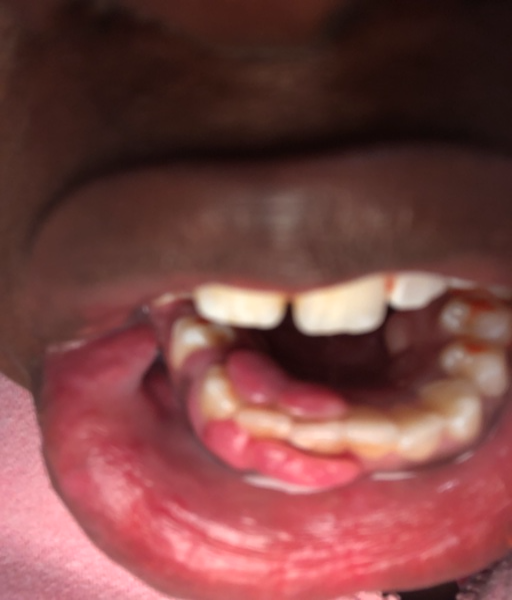

So for 4 weeks I've had this gone rouge canker sore. I'm getting it surgically removed in 2 months. It's so noticeable although it's in the inside of my bottom lip. I also wear bottom retainers and that makes the pain 2x worse. What can I do to reduce it or completely remove it. I've tried staying away from sugary or acidic food but that doesn't help, please help me.

Dental Professional

Unfortunately, this appears to be from trauma and will continue to get worse until it is removed.  The more inflammation, the easier it will be irritated.  If possible, try to move up your surgery appointment in order to reduce your waiting time.  Be sure to eliminate any acidic foods and regulary rinse with warm salt water.  You can placed orthodontic wax around your retainer to reduce the amount of rubbing against the sore as well.  There is also an over-the-counter medication called Tanac that can help to temporarily numb the sore and place a healing film over the top of it.